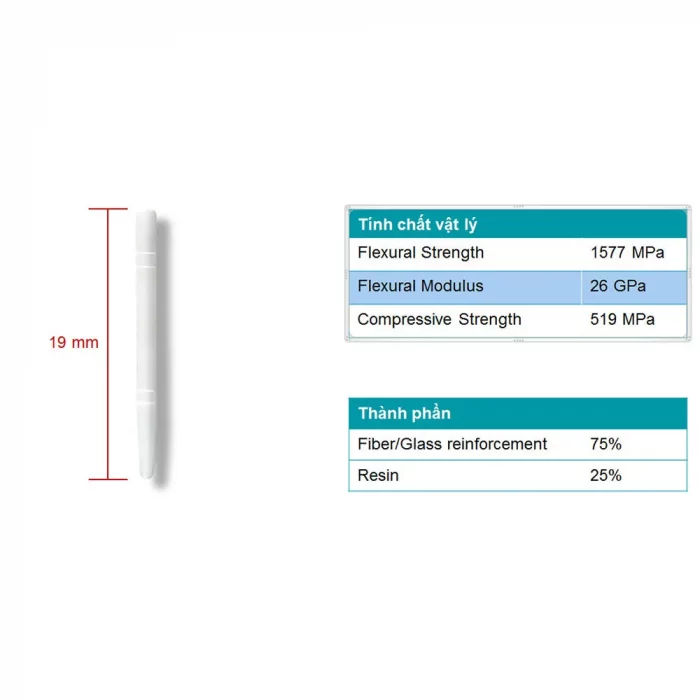

Fiber posts with high strength, high bending strength, and resistance to shearing force have an elastic modulus similar to that of dentin. It can absorb bite force and external forces to avoid root features. 4% taper in the bottom third. It is translucent hence light can pass through it while using a light cure.

Key specification –

- Flexural Strength – 1577 MPa

- Flexural Modulus – 26 GPa

- Compressive Strength – 519 MPa

Composition :

- Fiber/Glass reinforcement 75%

- Resin 25%

Dimensions of the Posts :

- Black – 1.1mm (diameter), 19mm length

- Yellow – 1.3mm (diameter), 19mm length

- Blue – 1.5mm (diameter), 19mm length